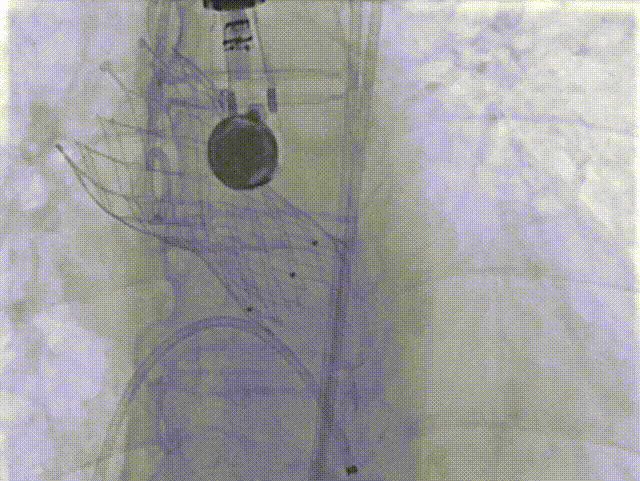

主动脉根部造影

18球囊预扩张